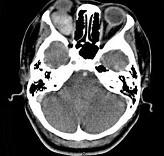

问题 41岁女性,右眼胀痛、眼球外突3月余,体检,发现低头时右侧眼球外突加重,CT检查如图所示,请选择最可能诊断()

选项 A.右侧眶内血管瘤 B.右侧眶内炎性假瘤 C.眼型格氏病 D.右侧眶内神经鞘瘤 E.右侧眶内皮样囊肿

答案 A